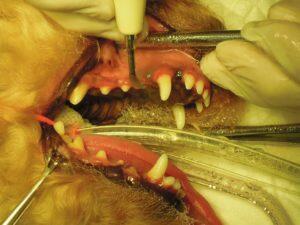

1.右側外観です。